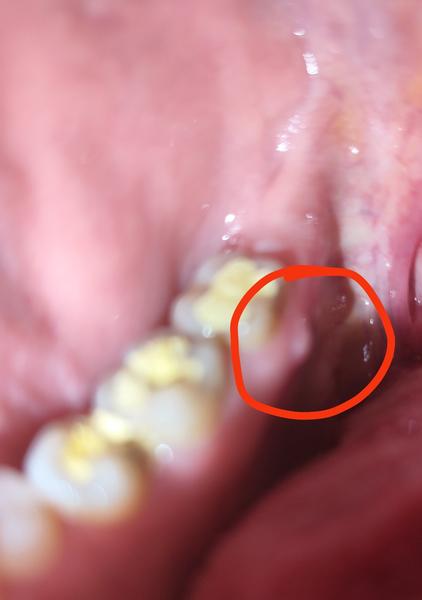

zo zufalstva sa obraciam ak takto na anonymnych cudzich ludi,uz dva mesiace sa trapim s ostrymi/rezavymi bolestami, vystreluju ako keby medzi sankou a uchom.Orl/neuro/odbery všetko negativne,CT,MRI atd tiez. Dva tyzdne do zadu sa mi spravila fistula na dasne z vnutornej strany (skusim foto pridat) aktualne je mega tvrda nesla zubarovi ani prepichnut ...tak beham po zubaroch,potesila som sa,ze konecne sa najde dovod z coho to je ,reku zapal v dasne/zube/koreni..avsak rtg aj 3d rtg neukazal ziadny zapal,obe stolicky pri fistule vyvrtal ,len drobne kazy boli a citila som vrtanie cize mrtve zuby nie su.. zubar sam nevie,z coho je fistula.. moze zapal vypalit takto aj z klbu celustneho? uzivam dva mesiace kurkumin,omega 3,zinok a rozne protizapalove veci mozno to potlaca nalezy netusim. Potesim sa akejkolvek rade /tipu, kedze to trva uz dlho a mam toho fakt dost ☹

@kattie1988 fistula bude s najväčšou pravdepodobnosťou zo zubu. Treba zistiť, ktorý zub spôsobuje problém a poriešiť ošetrenie korenovych kanálikov, poprípade extrakciu. Išla by som na konzultáciu k inému zubárovi, pozrieť medzizubné priestory, pod vypĺňami, proste treba nájsť zdroj infekcie.

@patus_2 dakujem za nazor,bola som u 3 zubarov 3 rtg a nikto tam nic nevidi..zuby dnes odvrtal plomby dal docasne a zajtra si volame co dalej.. ale vytahovat nervy,vyplnat kanaliky asi nema zmysel ked tam realne zapal nie je a zbytocne sa "zabiju" zuby :(

ja mam tiez taketo tvrde pri koreni zubu a nie je to fistula zo zapalu dr. mi tvrdi ze je to presvitajuci koren zuba - u mna mrtvy a niekedy boli desne tiez som si myslela ze fistula ale ze nie a na rtg zubov nie je vidiet zapal od korena? mne museli robit resekciu